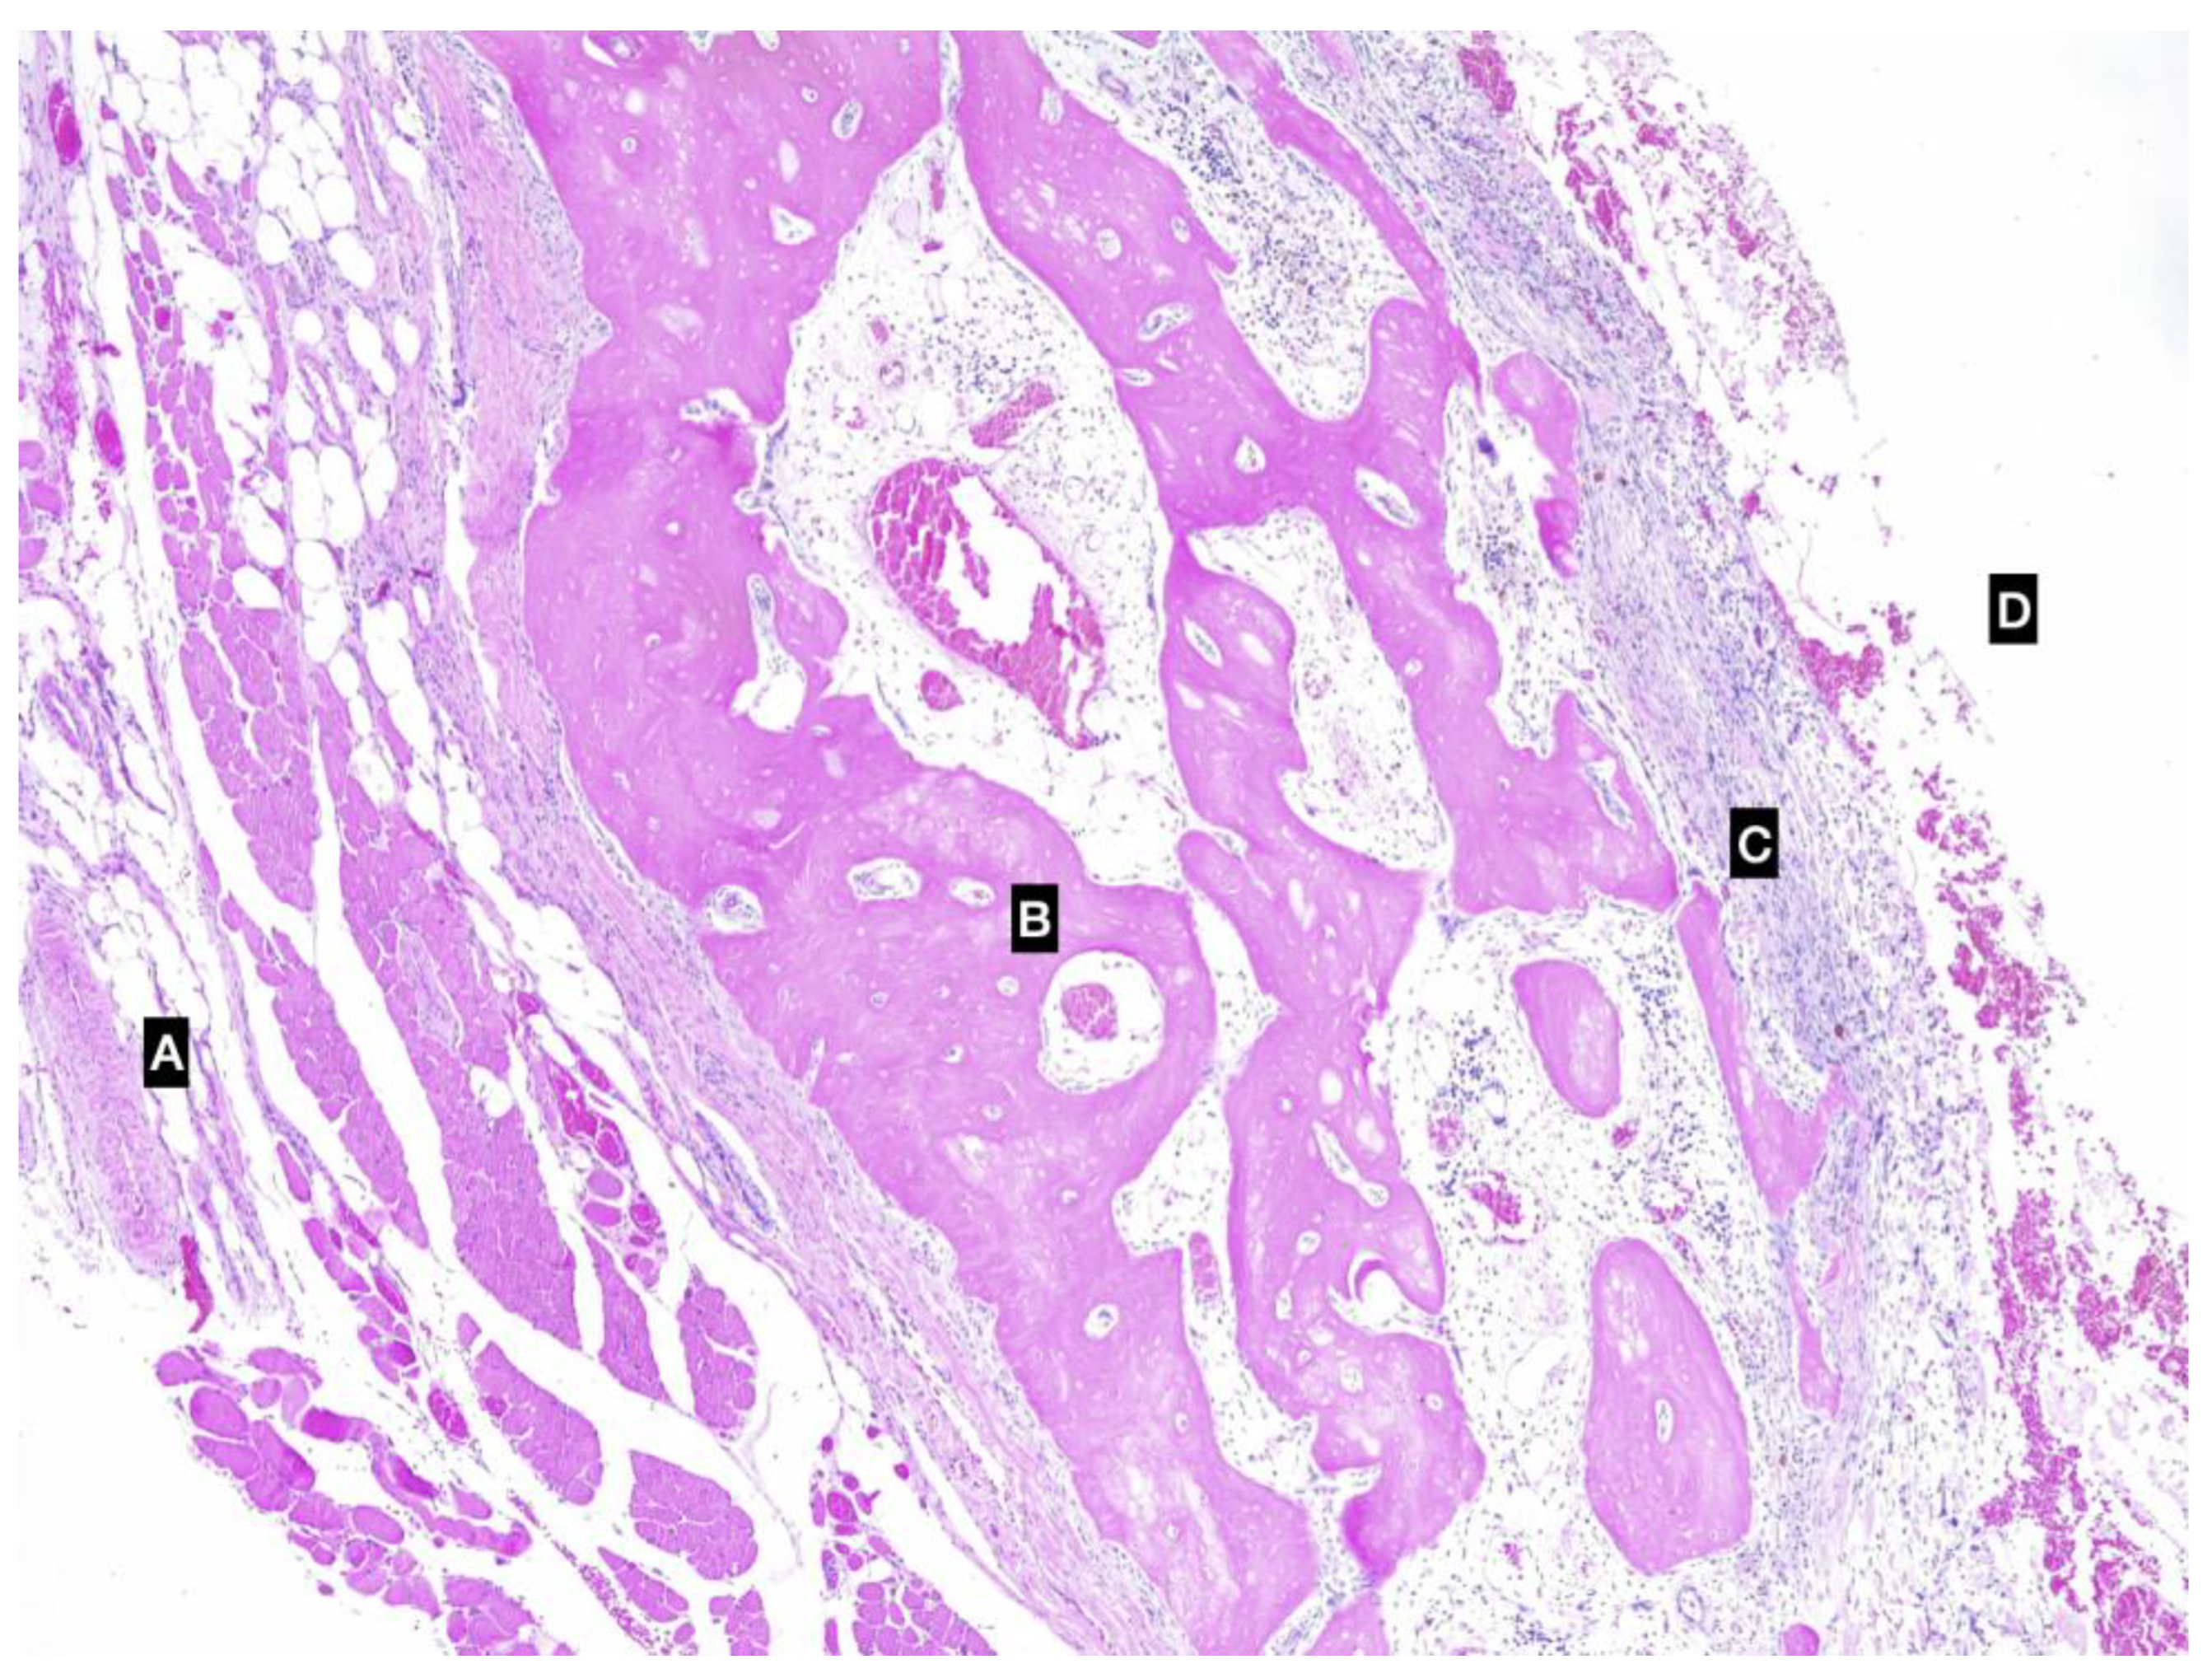

Histologically, the SGs showed multifocal moderate lymphoplasmacytic chronic sialoadenitis with the interstitial spaces expanded by thick bundles of fibrocytes (fibrosis). The cystic lesion was lined by granulation tissue and small foci of an osseous metaplasia (Figure 3). The lymph nodes removed were characterised by hyperplastic lymphadenitis.

Figure 3. Photomicrographs of the ossified cystic cavity. (A) external aspect of the pseudocyst, muscular layer; (B) bone tissue; (C) connective tissue of the pseudocapsule; (D) inner cavity. Imaging was conducted using a haematoxylin and eosin stain.